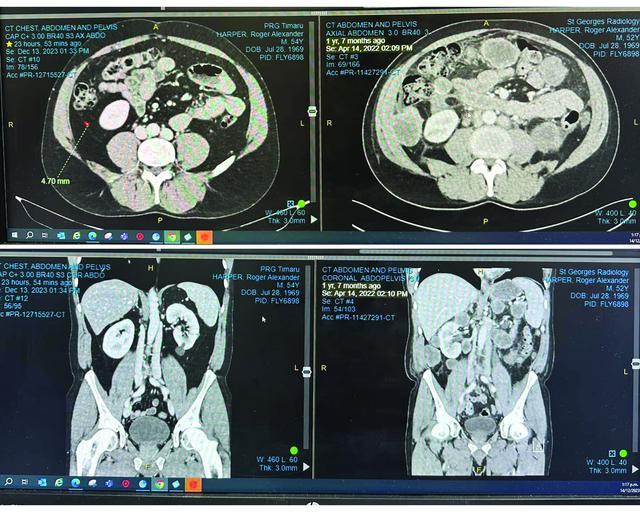

Roger has finished with Immunotherapy and has been declared CANCER FREE! He posted these words and images on Facebook in December. For those of you not on Facebook, here is his update.

"The CT scan images on the left were scanned in Dec 23. The images on the right are from the day before Apr 22. You'll see from the images on the right my abdomen was CRAMMED with tumours (shown as grey lumps) – it was this day that the oncologist gave me a month or so to live and said it was not prudent to have another infusion (had only had one at this stage). I insisted on a second infusion and the atmosphere got quite tense in his office but he gave in after I would not take no for an answer with an absolute and unwavering firmness. What did we have to lose apart from the 17k cost (which you generous people enabled)?